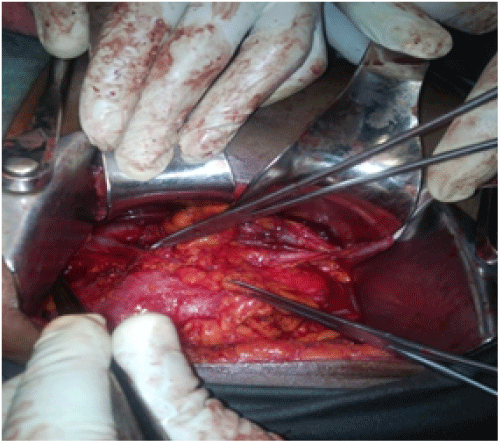

AMC is a 50-year-old female primary school teacher, with a past history of one cesarean section for her only child 28 years earlier. Her husband had died 4 years ago from an unknown splenic tumor. She presented with intermittent, massive, gross hematuria of 2 years duration. The patient was a non smoker and denied pain, fever, neither vomiting nor any lower urinary tract symptoms. She had however been treated as recurrent urinary tract infection until a few months ago, when she was referred to our urology department after presenting with progressive fatigue associated to the above symptoms. Except for pallor and prostration, physical examination was unremarkable. CT urogram showed right hydronephrosis up to the upper third of the right ureter on a non functioning kidney (figure 1). Neither a stone nor any obstructive lesion could be identified on the CT scan (Figure 1).

Figure 1A and 1B: CT scan revealed a right hydronephrosis.

CT scanning also can be used for determining the local extent of the u and presence of distant metastases, but is of limited value in predicting the pathologic stage of upper urinary tract urothelial tumours with an accuracy of 43-77%. In our case the CT scan was unable to detect the tumour and was reported as normal (Figure 1). Cystoscopy may help to localize bleeding site (left or right) and rule out or confirm concomitant bladder lesions. This test was useful in our investigations as stated in case report above.